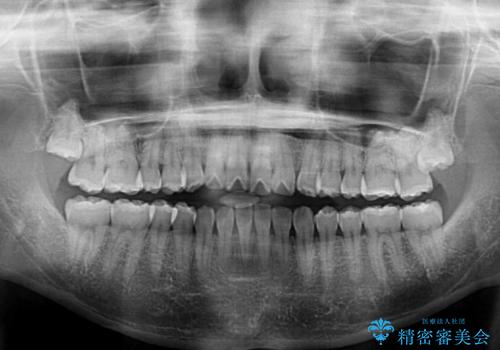

オープンバイトのインビザラインを用いた再矯正

- 矯正治療の後戻りを気にして来院された患者様です。

オープンバイト(前歯の開咬)と下顎骨の偏位による不正咬合が認められました。

骨格の偏位による不正咬合は改善しきれないことを理解いただいた上で、インビザラインにて矯正治療を行うこととしました。

オープンバイトは後戻りを起こしやすいため、極力そのリスクを軽減するため、奥歯を圧下させるように治療を進めていきました。

下顎骨の偏位が顕著であったため、上下の正中を合わせることはできませんでしたが、患者様には大変満足していただきました。